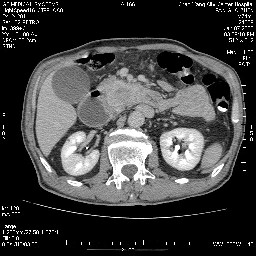

双肾多发小囊肿;左肾积水。

十二指肠水平段腔内占位伴梗阻,中等度较为均匀的强化,洗脱慢,区域淋巴结显示增多,符合腺癌表现。下腔静脉变异。

病变考虑为钩突癌。

支持十二指肠腺癌伴梗阻.,下腔静脉发育变异.

需除外12指肠水平段间质瘤。

十二指肠水平部腺癌伴梗阻并侵犯邻近结构。下腔静脉发育变异。

今日手术结果:胰腺钩突癌侵犯十二直肠,腹腔淋巴结转移.